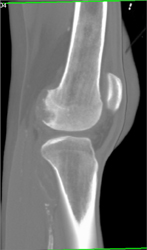

Avascular Necrosis (AVN) of Femur